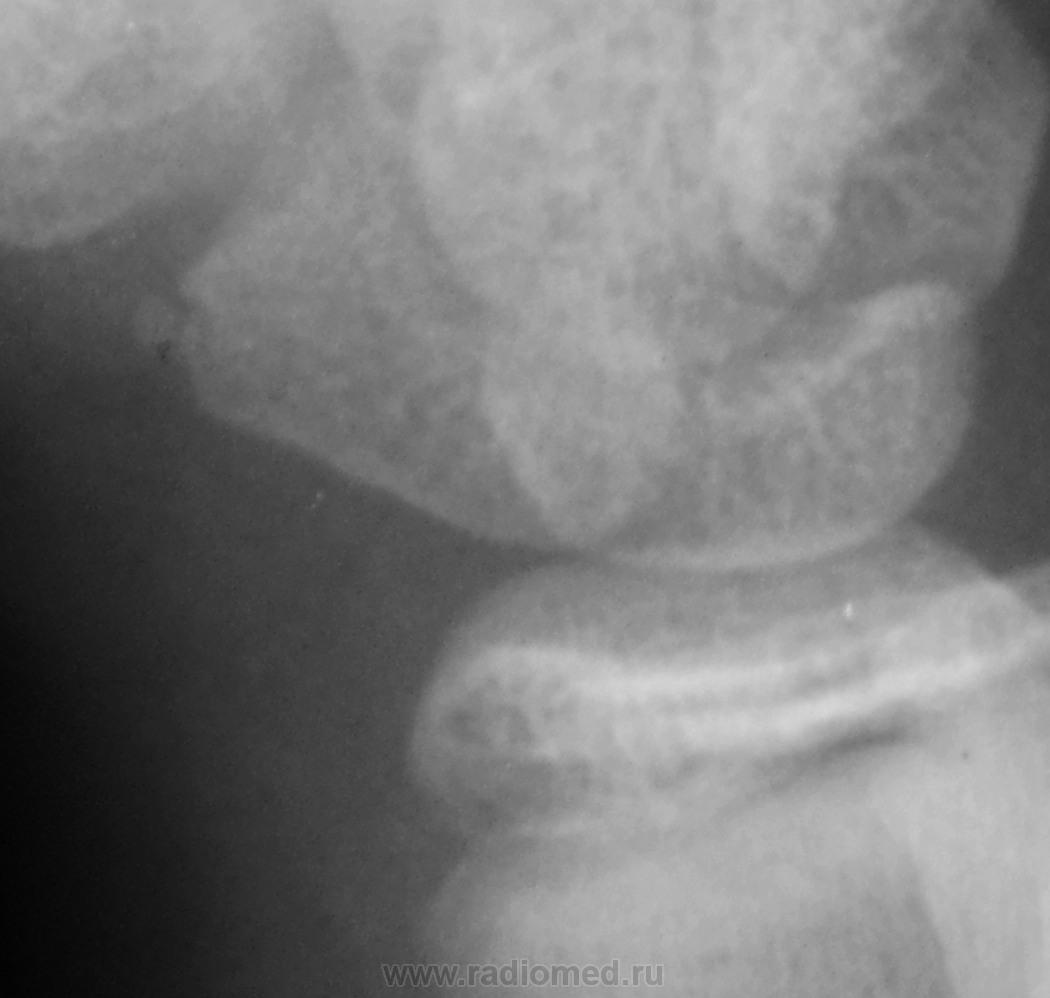

Осколок ладьевидной кости.

поднадкостничный перелом дистального метадиафиза лучевой кости....без смещения отломков...ладьевидная кость так не ломается.)  сверхкомплектная кость...сочетать с клиникой ..с локализацией болезнености.

Поднадкостничный перелом лучевой кости в нижней трети без смещения. Краевой перелом ладьевидной кости? Остеохондропатия ладьевидной кости?

Микрофокусная рентгенография ладьевидной кости? http://www.radiomed.ru/publications/kss-mikrofokusnaya-rentgenografiya-v-obsledovanii-kostno-sustavnoi-sistemy